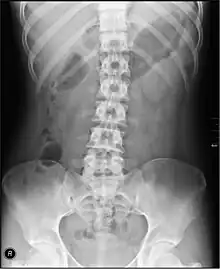

| Organs of the gastrointestinal tract | |